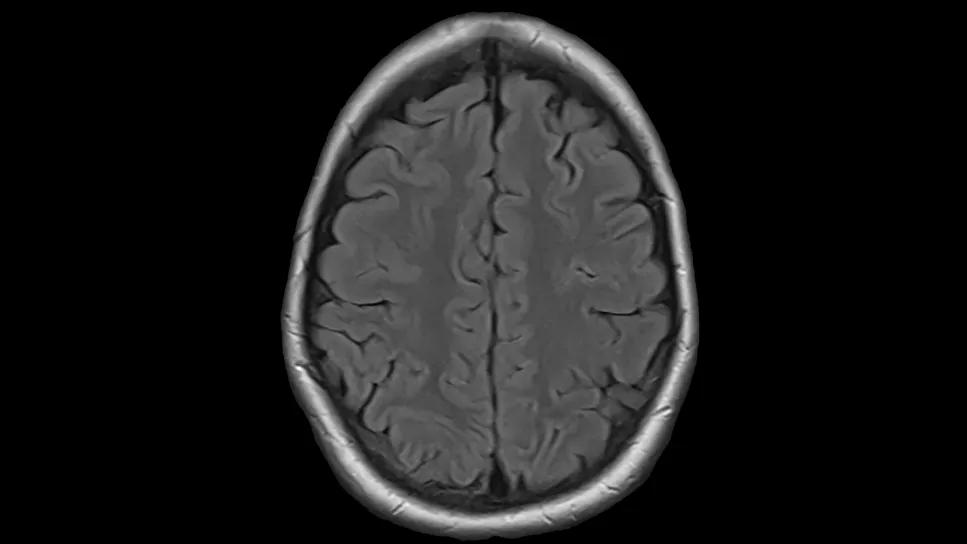

Before and after scan

A female college student was being treated for T-cell lymphoma at a nearby cancer center. Typically, patients with CD30 positive T-cell lymphoma respond to brentuximab vedotin-containing chemotherapy regimens. However, she was refractory within a month of starting this treatment, with new lesions in her brain. She was hospitalized with headaches, nausea and extreme fatigue.

Treating T-cell lymphoma in the brain required a creative approach. Dr. Jagadeesh decided to put the patient on a newer tyrosine kinase inhibitor that’s approved for patients with lung cancer with an anaplastic lymphoma kinase (ALK) mutation. This drug was used since her lymphoma also had this same genetic mutation. “There are case reports showing this drug delivers a good response in relapsed/refractory T-cell lymphoma patients with the ALK mutation, even with CNS disease,” says Dr. Jagadeesh.

Now nearly a year out from her bone marrow transplant, the patient is in complete remission. She is not on any maintenance therapy.